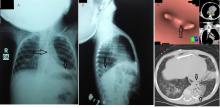

[3]Figure 1. VP shunt in the left lower lobe of lung piercing left copula of diaphragm. A and B) PA and lateral chest x-ray. C and D) MSCT chest, pulmonary and tracheobronchial reconstruction windows.

A 2-year-old girl with congenital hydrocephalus had a VP shunt that had been inserted from 1 year. The patient presented with recurrent chest infection and productive cough for 10 months. Also, she suffered from intermittent attacks of vomiting and diarrhea over 2 months duration. On evaluation, the patient was expectorating a clear watery sputum. A chest x-ray revealed radio-opaque catheter emerging from the abdomen into the left lower hemithorax. Chest computed tomography revealed abnormal migration of the VP shunt in the left lower lobe of lung and piercing left copula of diaphragm, with bronchiectatic changes and pneumonic consolidation of left lower lung lobe.